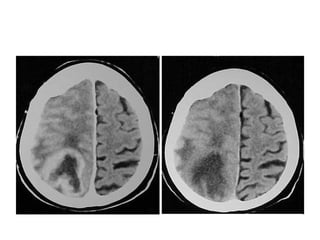

Meduloblastoma(imagem)

• TC – 50%, lesão bem definida, hiperdensa e

hipercaptante

– Linha média

– Preenchimento do IV ventrículo(canal medular e III

ventrículo)

– Cistos; necrose

– Hidrocefalia obstrutiva

• RM

– Definiçao mais precisa dos limites

– Hipointensa em T1 e hiperintensa em T2

– Melhor detecção de metástases